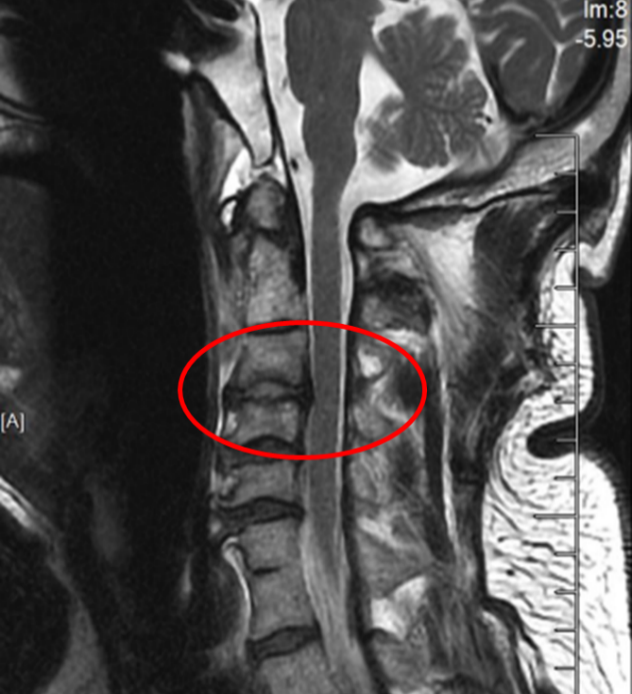

图2:术后正侧位片

在麻醉手术科的严密监护下,刘义杰副主任医师首先熟练地完成了颈椎前路C3-4减压融合术(ACDF),成功解除了脊髓的压迫。然而,通过同一个仅3厘米的微小切口,精准地将螺钉植入游离且向后倾倒的齿状突具有极大的挑战性。关键时刻,骨科手术机器人发挥了“超级助手”的作用。团队利用机器人导航系统,对进钉点和角度进行了反复测算与调整,导针精准抵达目标。随后,由姜为民主任专利研发的一枚新型齿状突螺钉顺着通道顺利旋入,牢牢锁住了骨折端。整个过程出血量少,手术顺利完成。

患者侯师傅术后苏醒后,原本瘫痪的四肢便能恢复活动。术后第一天,他的四肢肌力已恢复至4级左右;术后第二天,他便能在定制颈部支具的保护下起床进行功能锻炼。从近乎全瘫到重新站立,其间仅经过短短两天时间。患者及家属对治疗效果激动不已,表示感谢。